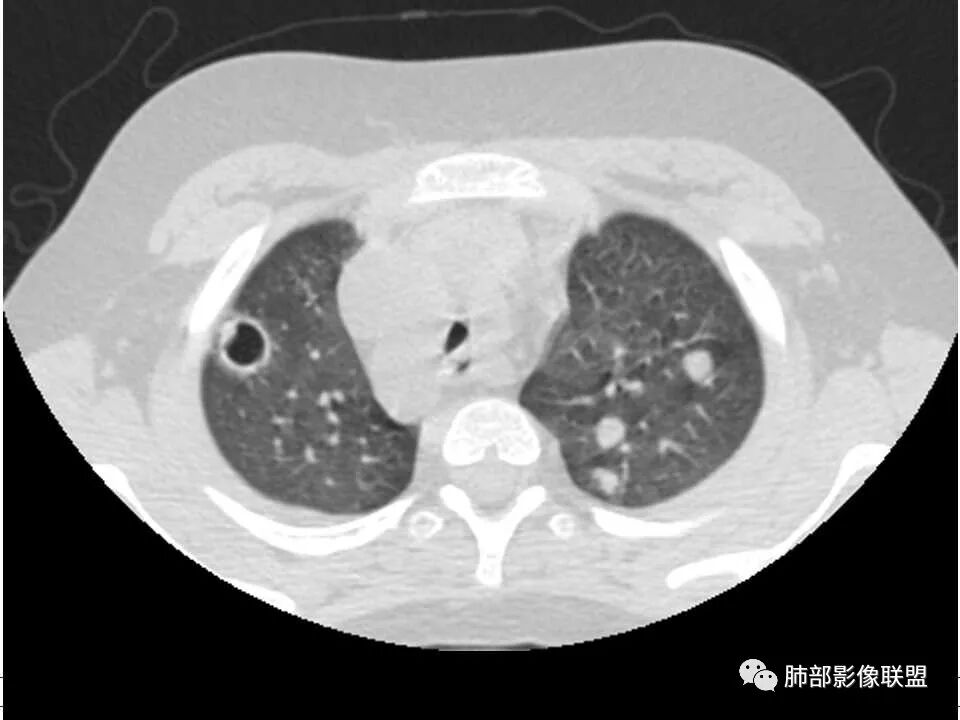

儿童患者,右下肢肿痛、发热起病,血象升高,双肺多发结节影,右肺结节并囊腔或空洞,左肺多发实性结节以胸膜下分布为主,考虑感染性病灶,有右下肢肿胀,需考虑蜂窝织炎, 血源性肺播散,金葡感染可能性大?

双肺多发结节,空洞,与胸膜相连,血道来源,空洞内壁光滑,结节周围模糊,考虑金葡菌感染。

男,8岁,两肺多发随机分布结节空洞影,壁光整,考虑血道来源,结合右侧膝关节有骨髓水肿信号,临床感染指标明显增高,考虑骨髓炎并血道播散,金葡菌感染?LCH小孩骨头症状相对较轻,放在代排吧。

小儿,急性起病,下肢疼痛,mr提示骨髓水肿,临床化验炎性指标高,考虑金葡菌骨髓炎,双肺多发结节,以血管支气管束及胸膜下分布为主,部分结节近端与血管相连,部分结节可见空腔,内壁光整,部分囊腔有张力,考虑骨髓炎并肺内血播感染,金葡?

2.双肺多发片影,随机分布,多空洞或囊腔,胸膜下多楔形影,气道未见受累等等符合脓毒血症影像学表现,尤其是金葡。

2、脓肿:实变区内脓肿,最常见吸入性金葡菌引起的多,下叶多见,在实变区中央,外壁不清,内壁光滑,可见气液平面;血源性脓肿,多发,结节状,大小无差异,边清,光滑,壁薄;

金葡菌的脓肿很少融合成团。